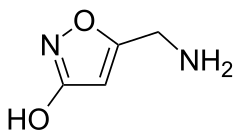

The major toxins involved in A. muscaria poisoning are muscimol (3-hydroxy-5-aminomethyl-1-isoxazole, an unsaturated cyclic hydroxamic acid) and the related amino acid ibotenic acid. Muscimol is the product of the decarboxylation (usually by drying) of ibotenic acid. Muscimol and ibotenic acid were discovered in the mid-20th century.[71][72] Researchers in England,[73] Japan[74] and Switzerland[72] showed that the effects produced were due mainly to ibotenic acid and muscimol, not muscarine.[15][71] These toxins are not distributed uniformly in the mushroom. Most are detected in the cap of the fruit, a moderate amount in the base, with the smallest amount in the stalk.[75][76] Quite rapidly, between 20 and 90 minutes after ingestion, a substantial fraction of ibotenic acid is excreted unmetabolised in the urine of the consumer. Almost no muscimol is excreted when pure ibotenic acid is eaten, but muscimol is detectable in the urine after eating A. muscaria, which contains both ibotenic acid and muscimol.[54]

Ibotenic acid and muscimol are structurally related to each other and to two major neurotransmitters of the central nervous system: glutamic acid and GABA respectively. Ibotenic acid and muscimol act like these neurotransmitters, muscimol being a potent GABAA agonist, while ibotenic acid is an agonist of NMDA glutamate receptors and certain metabotropic glutamate receptors[77] which are involved in the control of neuronal activity. It is these interactions which are thought to cause the psychoactive effects found in intoxication.[17][55]